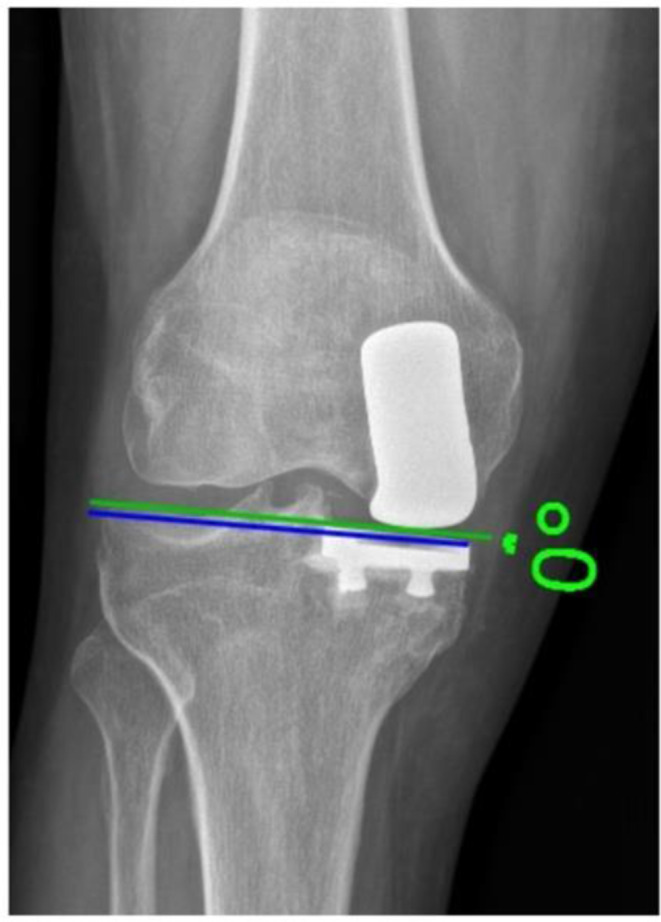

Methods: This retrospective study analyzed 63 patients with cemented medial UKAs with a minimum follow-up of five years. Patient-reported outcomes (PROMs) included the Oxford Knee Score (OKS). Radiographic parameters assessed were: PTS, mechanical axis, prosthetic joint space height, tibial component obliquity, intraprosthetic divergence, and tibial periprosthetic radiolucency. Partial Pearson correlation and multiple linear regression analyses were used to evaluate the relationship between tibial periprosthetic radiolucency and demographic or radiographic parameters.

Results: Of 63 patients (mean age 68.9 ± 7.9 years, follow-up 62.5 ± 8.8 months), 5 knees (7.9%) demonstrated tibial periprosthetic radiolucency ≥ 2 mm. The mean postoperative PTS change was 3.8 ± 2.6°, mechanical axis change: 2.5 ± 1.8°, prosthetic joint space height: 9.2 ± 3.1 mm, tibial component obliquity: 2.5° ± 3°, and intraprosthetic divergence angle: 5° ± 4°. OKS averaged 43.9 (range 22-48), with a mean knee flexion of 123.4 ± 6.8°. Statistical analysis showed no significant associations between tibial periprosthetic radiolucency and demographics, radiographic parameters, or PROMs. Changes in PTS did not correlate with a range of motion (ROM), PROMs, or radiolucency.